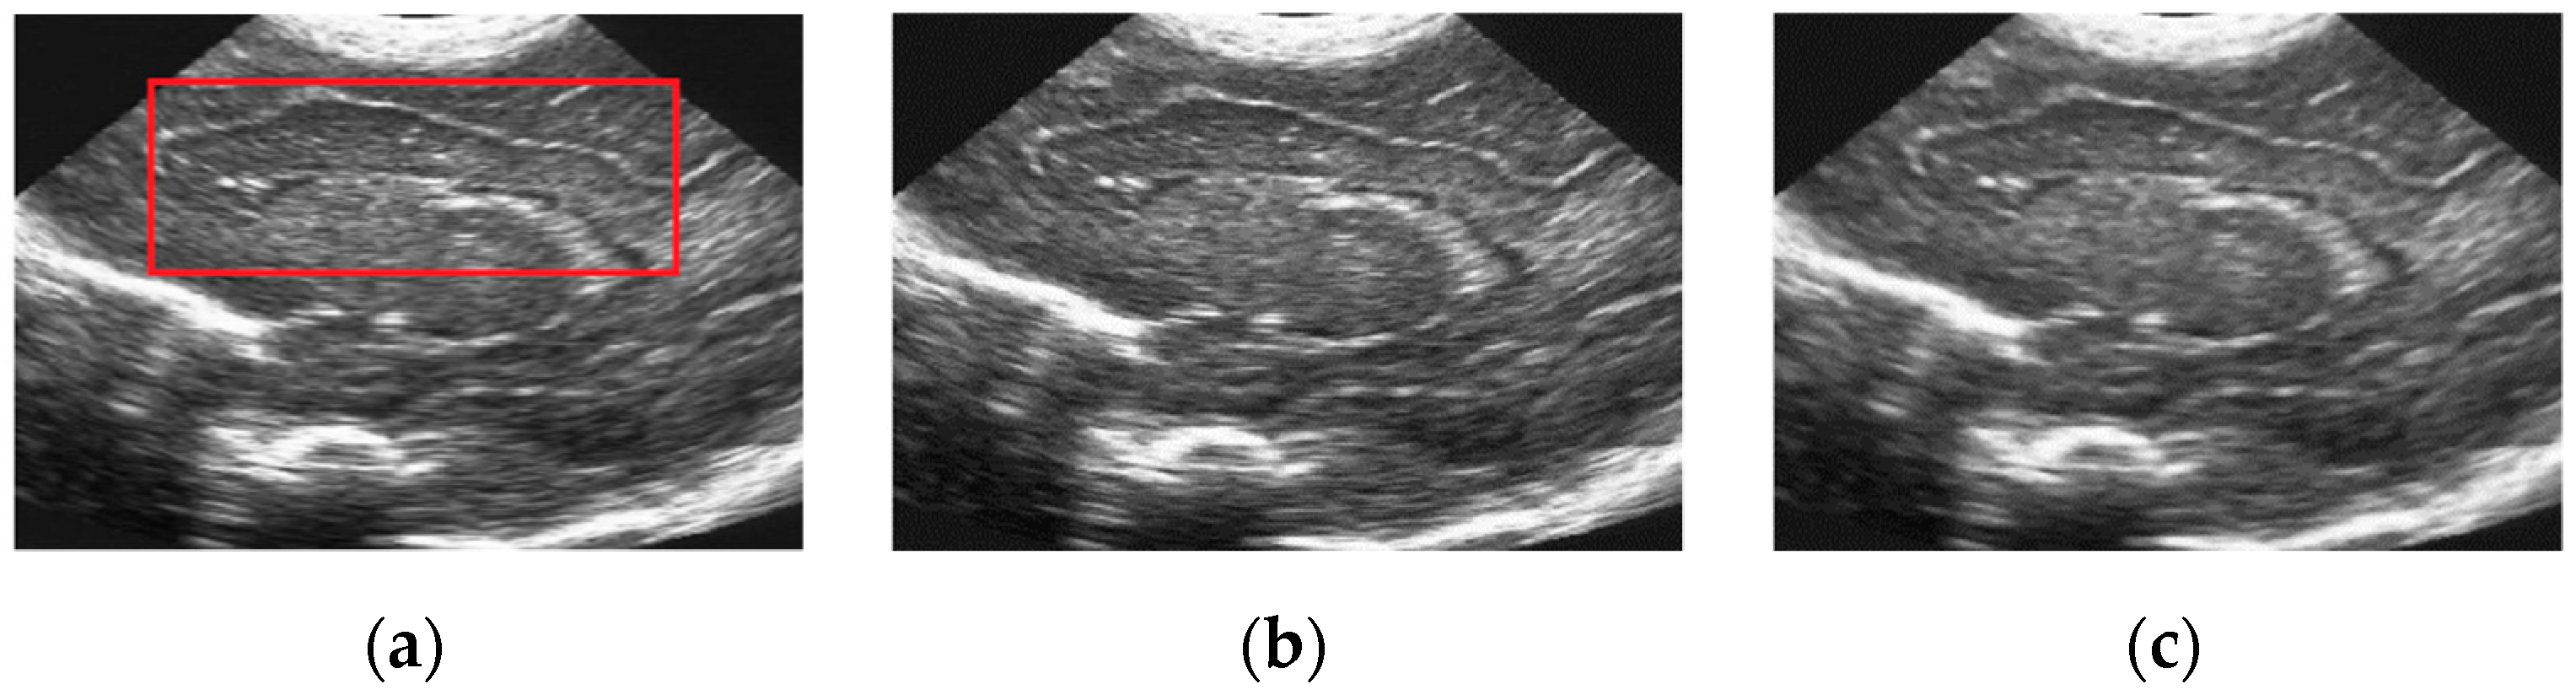

5.2. Real Ultrasound Image Denoising Experiment

5.2.2. Experimental Results